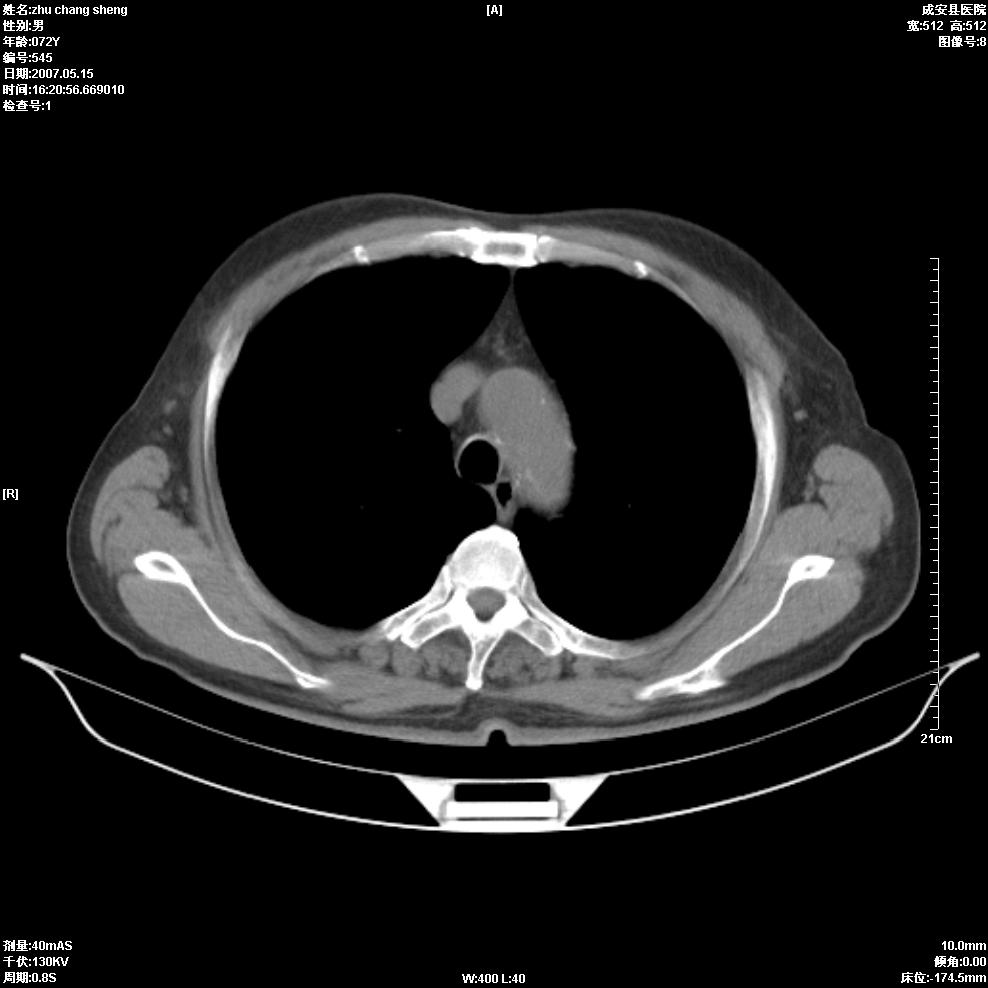

以下是引用医博云天在2007-5-15 19:10:00的发言:[br]心包积液,胸腔积液,心影增大,左心为主。

以下是引用zhangzhongshou在2007-5-15 20:21:00的发言:[br]心包积液可以肯定有,肿块显示不清,建议增强或mri检查。

以下是引用jinning在2007-5-15 21:06:00的发言:[br]心包积液可以肯定,建议增强或mri检查吧!

以下是引用拾荒者在2007-5-15 22:28:00的发言:[br]心包膜增厚,有少量积液,右室前壁示均匀软组织密度影,边界欠清,建议增强扫描或mri检查与室壁瘤鉴别。

以下是引用还珠格格在2007-5-19 9:50:00的发言:[br]病人与5月18日 做了核磁增强扫描 确诊为前上纵隔侵袭性胸腺瘤。